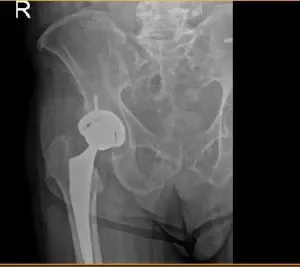

Radiografía postoperatoria de cadera

Las imágenes postoperatorias muestran artroplastia total de cadera derecha, en buena alineación, cambios degenerativos sacroilíacos leves. El paciente volvió para una cita postoperatoria para la extracción de la grapa y el pronóstico es bueno, gracias a una cirugía sencilla. El paciente cumple con el programa de fisioterapia ambulatoria y soporta peso completamente bilateralmente.